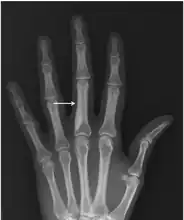

Osteopoikilosis

Melorheostosis

Note thickened sclerotic cortical bone